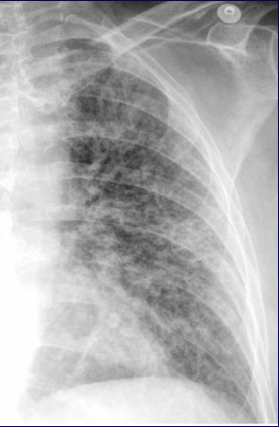

Fibrose pulmonaire : approche diagnostique et cas cliniques

• Fibrose pulmonaire  approche diagnostique et cas cliniques

• Fibrose pulmonaire : approche diagnostique et cas cliniques